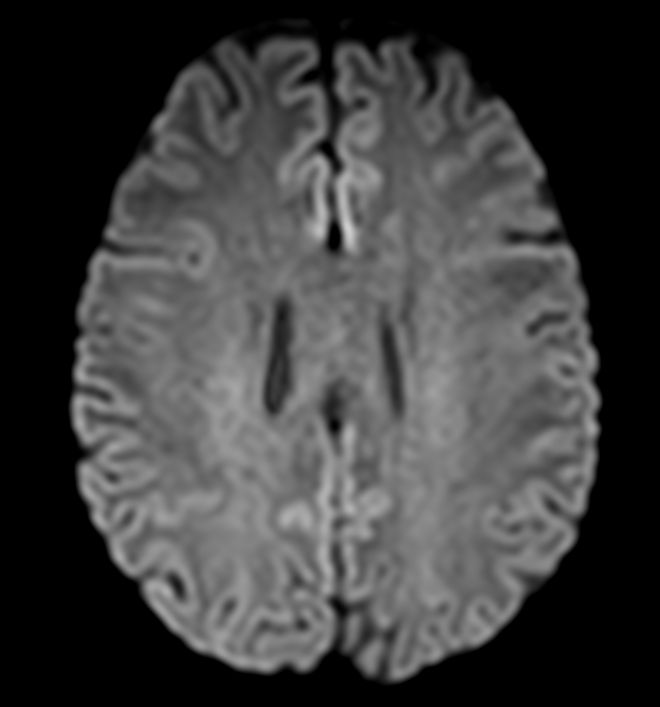

Diffusion b1000

Diffusion b1000 (ADC)